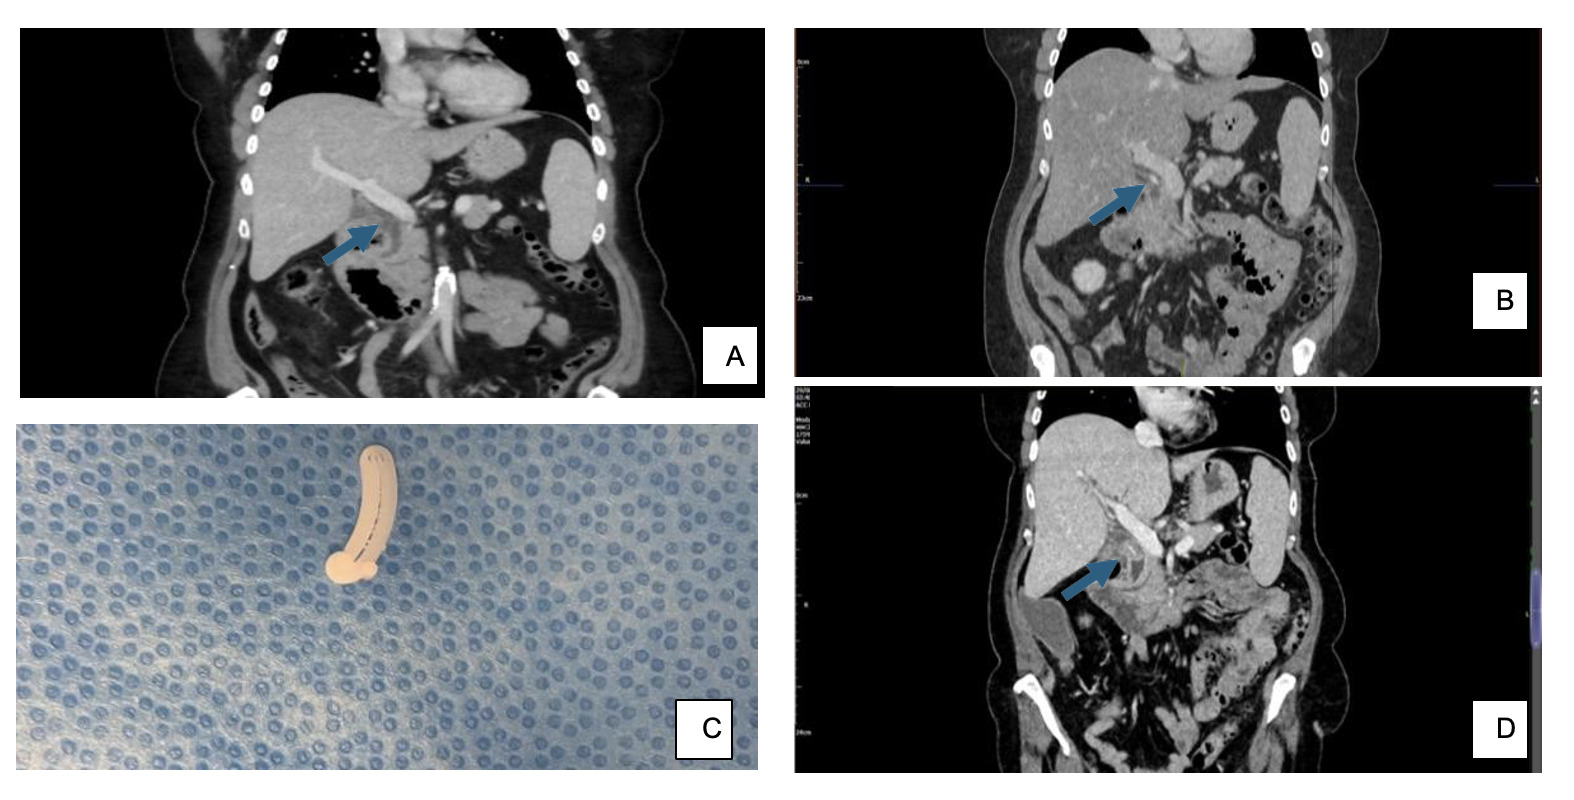

A 61 female presented with recurrent bile duct stones, leading to biliary sepsis and pancreatitis. Her past medical history included the excision of a D2/D3 duodenal Gastro-Intestinal Stromal Tumour (GIST) in 2016. She subsequently underwent laparoscopic cholecystectomy and Common Bile Duct (CBD) exploration with T-tube insertion in 2020 due to previous CBD stones, with full recovery. Prior to this, imaging showed CBD dilation but no hem-o-lok® clip (Fig 1, Panel A). However, a hem-o-lok® clip is present post-cholecystectomy scan in 2021 and 2024 (Fig 1, Panel B and Panel D). She was admitted in 2023, severely unwell due to pancreatitis from recurrent CBD stones. To retrieve her CBD stones, she underwent multiple ERCPs, including rendezvous procedures, which failed due to post- duodenectomy scarring and a duodenal diverticulum. After initial conservative management and discussion at a benign HPB multidisciplinary team in Oxford, she underwent an open CBD exploration showing the presence of a large CBD stone with a nidus: which was the hem-o-lok® (Fig 1, Panel C). This was present from the time of her cholecystectomy in 2020 (based on retrospective review of serial radiology), which is likely to have slipped into the CBD.

Although there have been a few case reports of a hem-o-lok® clip migrating to the CBD from the time of laparoscopic cholecystectomy,1,2 including a case after CBD exploration,3 this occurrence is exceedingly rare. These photographs show the presence of the clip in preoperative serial CT scans. This case highlights the importance of careful history gathering and examination of CT imaging. It would be imperative to communicate to radiologists that hem-o-lok® clips can cause recurrent stones and should be looked for within the CBD. Patients can also be counselled for this potential risk of laparoscopic cholecystectomy at the time of the procedure.